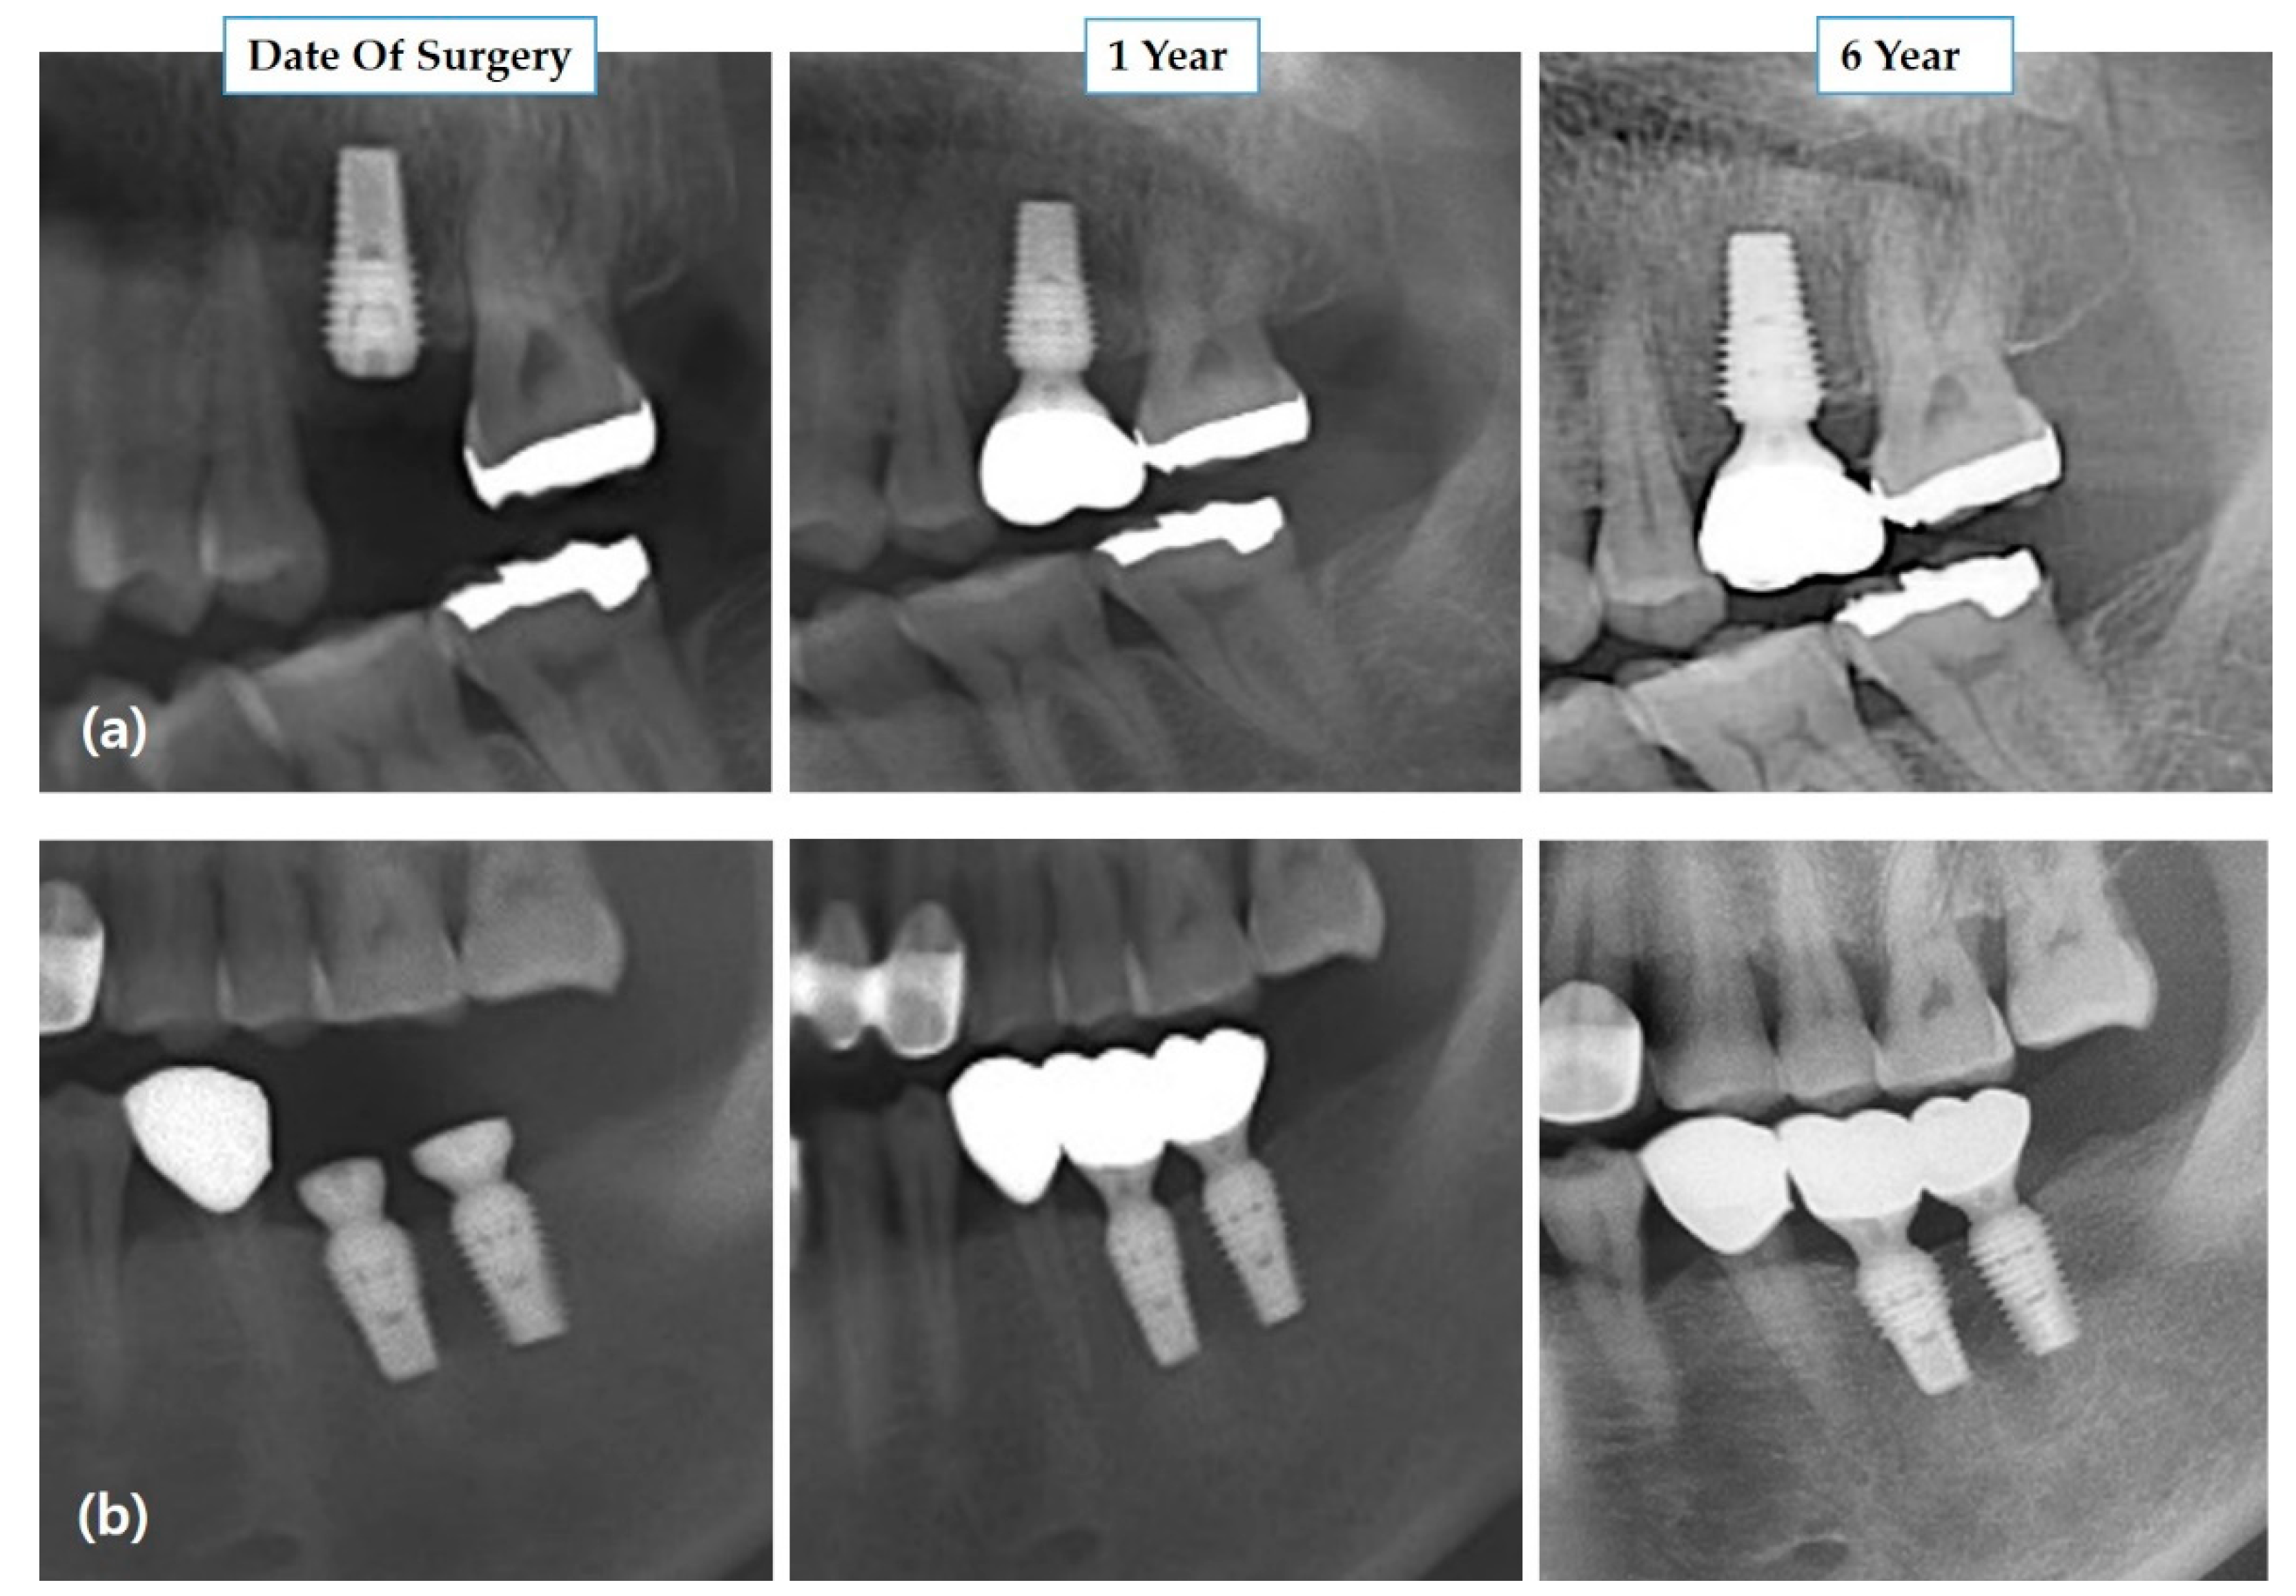

2.3. Measurement of Marginal Bone Levels and Implant Survival

3.2. Marginal Bone Level